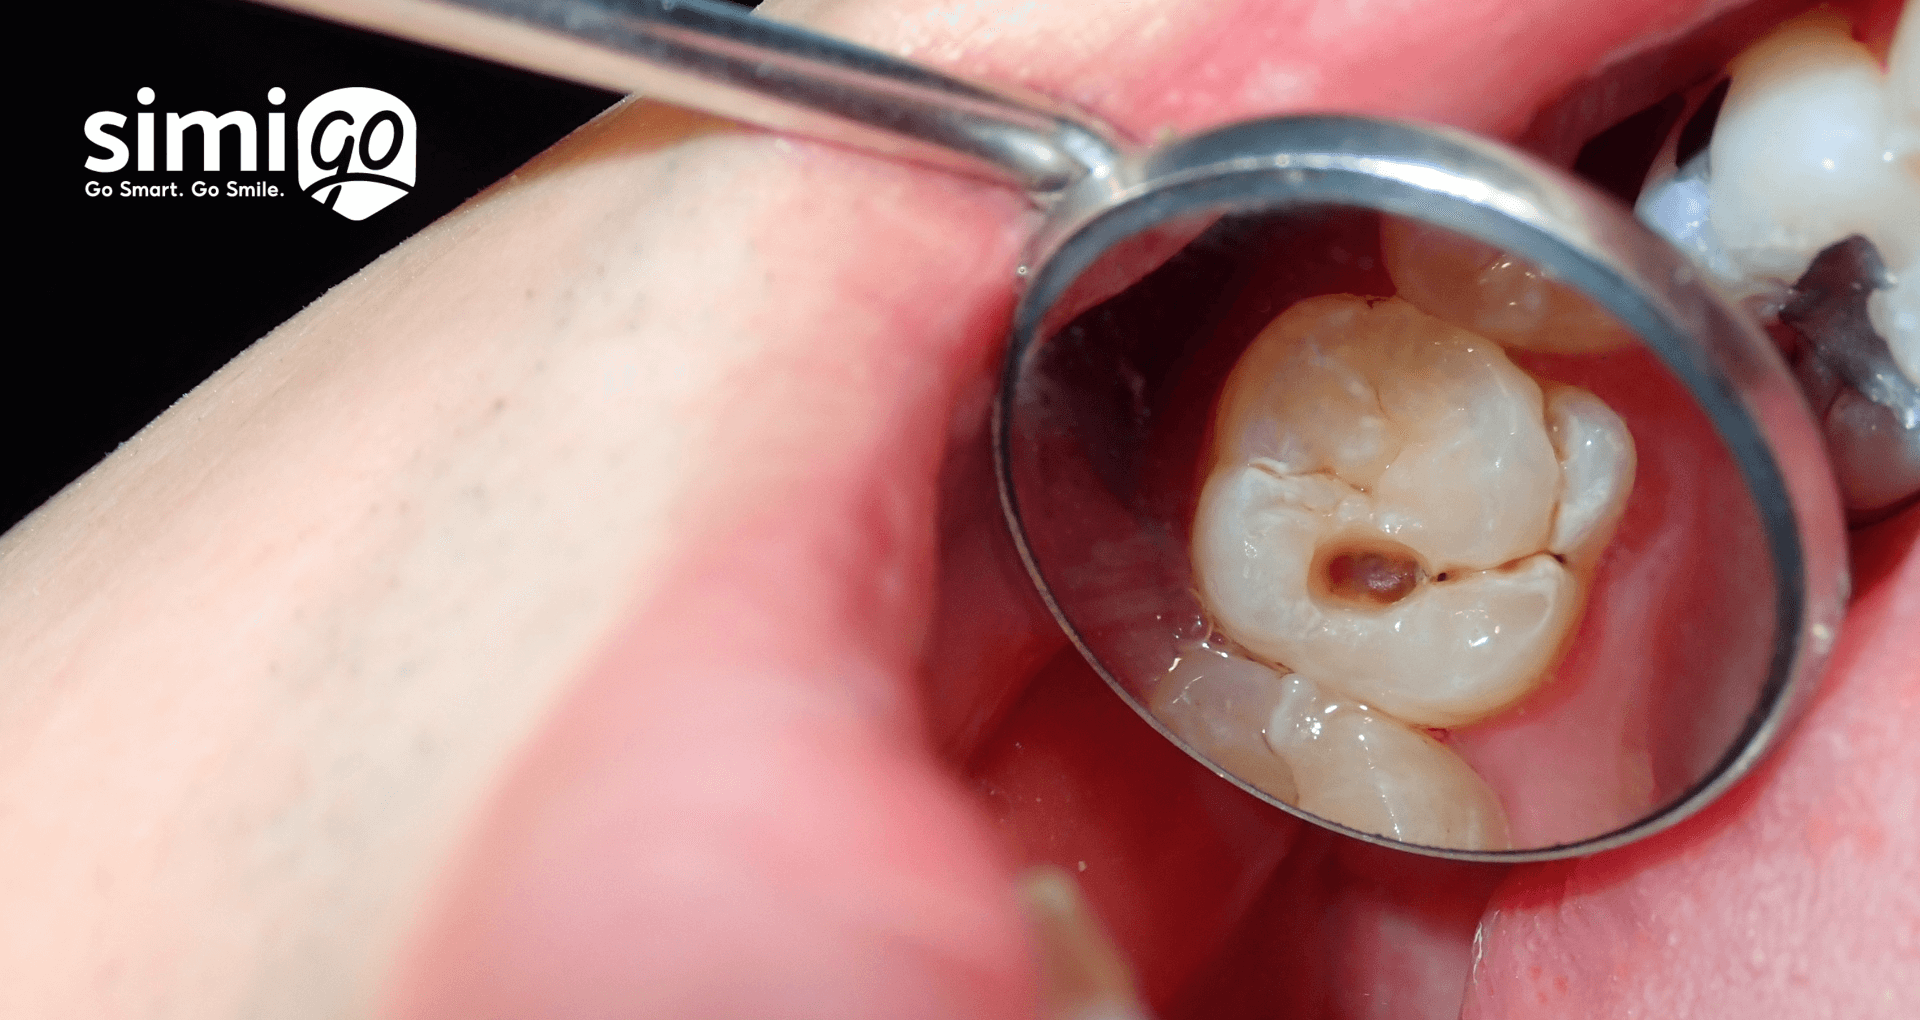

Mảng bám răng là lớp màng mỏng gồm vi khuẩn, vụn thức ăn và tế bào chết bám trên bề mặt răng. Sau mỗi bữa ăn, nếu không vệ sinh đúng cách, chúng nhanh chóng tích tụ thành một lớp dính chặt, không thể rửa trôi bằng nước thông thường.

Ban đầu, mảng bám chỉ là lớp màng mịn, nhưng chỉ sau vài ngày, nó trở nên dày hơn và cứng lại, hình thành cao răng – kẻ thù khiến men răng yếu dần, hơi thở có mùi và nướu bị viêm sưng.

Nguy hiểm hơn, mảng bám không chỉ gây mất thẩm mỹ mà còn mở đường cho hàng triệu vi khuẩn tấn công sâu vào lợi và chân răng, gây ra viêm nha chu – nguyên nhân hàng đầu dẫn đến rụng răng sớm.

Không chỉ vậy, acid do vi khuẩn tiết ra còn bào mòn men răng, tạo điều kiện cho sâu răng phát triển. Các vùng bị mảng bám phủ kín cũng dễ tổn thương hơn khi ăn uống, khiến răng ê buốt, đau nhức hoặc đổi màu.

Một điều đáng lo ngại là mảng bám có thể lan rộng dưới nướu, gây viêm lợi, tụt lợi và tiêu xương hàm nếu không được xử lý kịp thời.